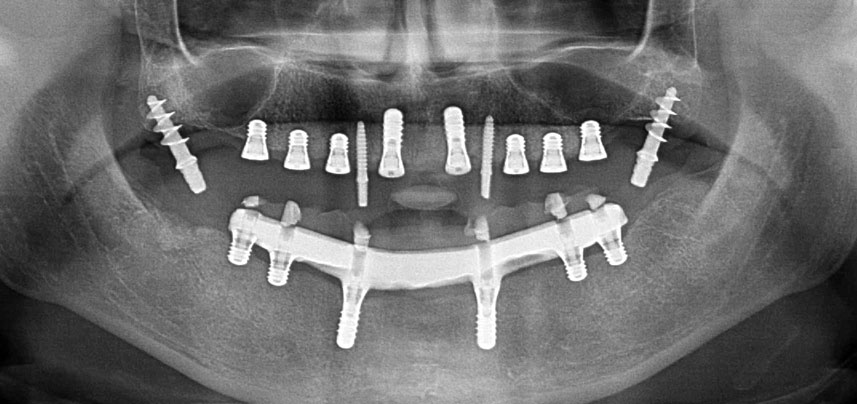

Postoperative Panoramaschichtaufnahme

Abb. 10: Die postoperative Panoramaschichtaufnahme zeigt alle Implantate an den richtigen Positionen, einschließlich der temporären Implantate in der Pterygoid-Region.

Wegen des relativ harten Knochens (D2) an den Positionen 11 und 21 wurden die 10 mm langen Implantatlager in diesem Bereich abschließend mit einem 4-mm-Spiralbohrer, dem chirurgischen Winkelstück WS-75 L von W&H und dem W&H Implantmed Implantologiemotor in Verbindung mit dem optionalen W&H Osstell ISQ module präpariert. Im Gegensatz dazu wurde der weiche Knochen der Implantatlager im Seitenzahnbereich mit dem Piezomed I3P auf den abschließenden Durchmesser von 3 mm erweitert. Die Implantate wurden dann transgingival eingesetzt, die Einheildauer betrug drei Monate (Abb. 6-10). Die vorhandene Prothese wurde auf vier provisorischen Implantaten abgestützt (Abb. 8).

Abb. 8: Nach Befestigung der Gingivaformer werden an den Positionen 18, 12, 22 und 28 provisorische Implantate eingesetzt.